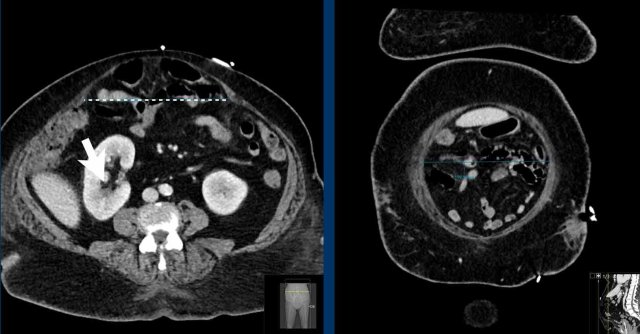

This is another example of a closed loop obstruction within the hernia sac.

The white arrow indicates the first obstruction, where the bowel enters the closed loop.

The yellow arrow indicates the exit.

In this case the closed loop is caused by adhesions within the hernia sack.

Notice the fat infiltration and the dilated loops with slightly hyperdense walls.

These are all signs of bowel ischemia.

Immediate laparotomy was performed.

The bowel within the hernia sac was ischemic and had a purple color, but after cleavage of the adhesions, the color of the bowel returned to normal.